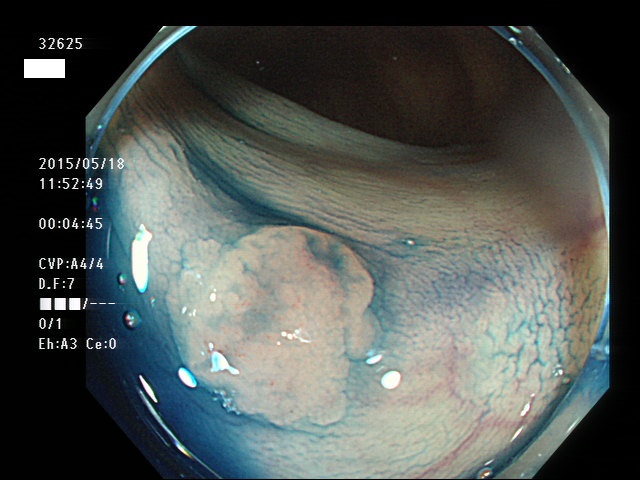

上記100名より抽出した平坦・陥凹型腺腫(=癌化の危険が高いが見落としやすい病変)の内視鏡写真